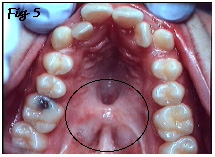

L'articulé croisé résulte d'une croissance de l'arcade supérieure insuffisante dans le sens transverse (en largeur). Cette insuffisance est causée par la présence de tissu cicatriciel. Ce tissu cicatriciel constitue l'une des séquelles des premières opérations de fermeture de la fente durant la prime enfance (Fig.5, zone cerclée en noir).

Ces cicatrices sont responsables de tensions sur le palais durant son développement. La croissance du palais peut en être plus ou moins affectée (ralentie), suivant l'ampleur de ces tensions cicatricielles. Un articulé croisé en est, souvent, la conséquence dentaire.